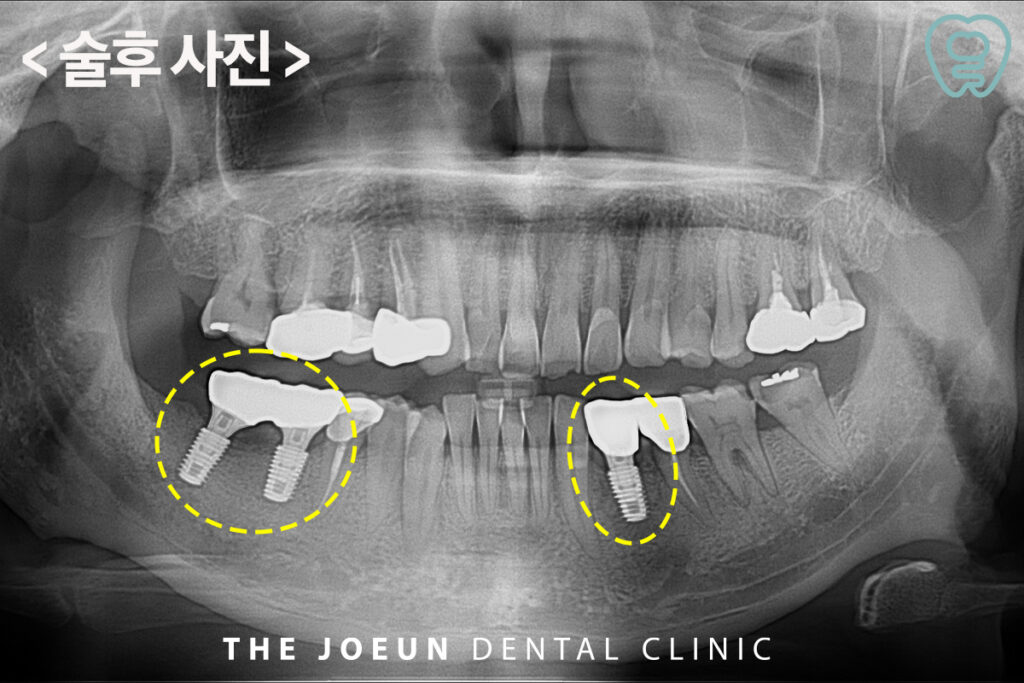

뼈이식을 하고 약 6개월 뒤, 검진 후 임플란트 식립을 진행하였습니다.

잇몸뼈가 심하게 파괴되어 걱정했지만 안정적으로 최종 보철물까지 완료하였습니다.

잇몸뼈가 부족한 경우라도 적절한 뼈 이식 치료를 거치면 임플란트가 가능합니다. 환자분의 상태에 따라 적절한 이식 재료를 선택하는 것이 중요하고, 시술 후에도 정기적인 검진과 구강 위생 관리가 필요합니다.